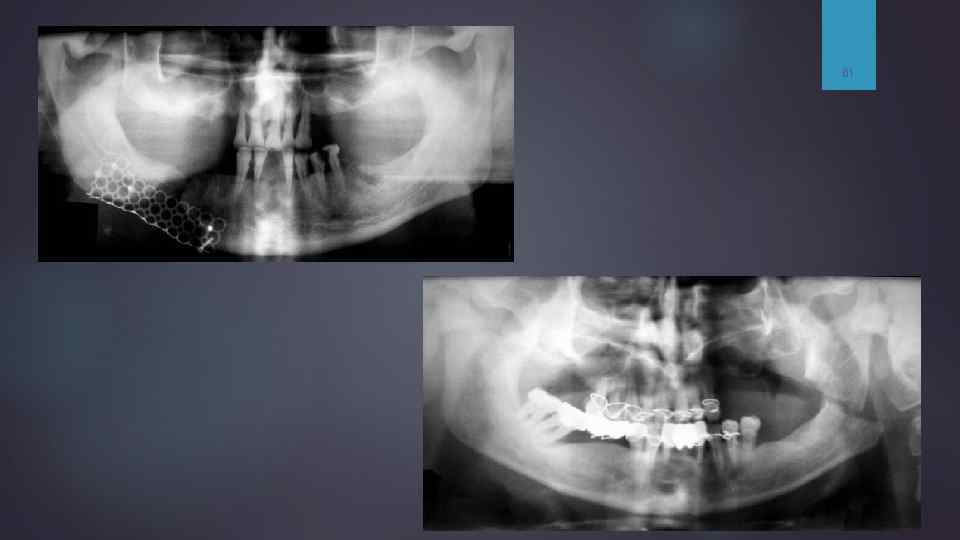

На рентгенограмме определяется перелом нижней челюсти. Отмечается деформация контура угла нижней челюсти с линией просветления (зона перелома), наложена иммобилизирующая шина.

Ортопантомограмма. Двусторонний перелом тела нижней челюсти — линия перелома справа проходит между 6 и 5, слева — в области угла. Отломок смещен вертикально.